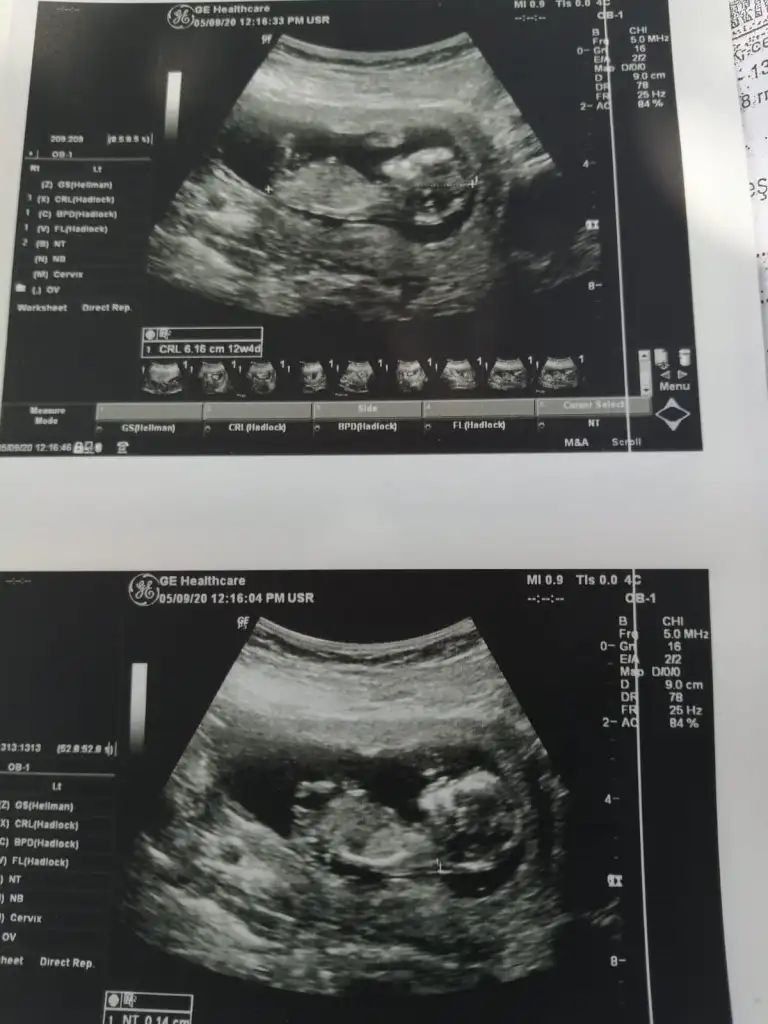

Erkek canım bu.önceki usg de kıza benzettim demiştim sanırım.bu usg de nub çizgisi çok belli bebiş bariz erkek.doktor birşey söyledimiKızlar yeni görüntü 12+4 tahmin rica edebililirmiyim

Erkek erkek.önceki usg de bu kadar belli değildi nub.tabi doktor daha iyi bilir hayırlısı olsundr göbek bağı sürekli arada olduğundan çok net bişey söyleyemiyor.Bazı kızların kilitorisi çok baskın olduğundan pipi gibi görünebiliyormş bu nedenle 2 hafta sonra dedi cnm

Doktor tahmin etmiştir erkek diyorumKızlar yeni görüntü 12+4 tahmin rica edebililirmiyim

Kız senesi kız topigi diyerek bu bebişin de kız olduğunu düşünüyorumEki Görüntüle 2300756

Kızlar bu yeni görüntü diğerinden 5 gün sonra 12+2 nubu belli olmuyor demiştiniz umarım bunda bellidir tahminlerinizi bekliyorum.